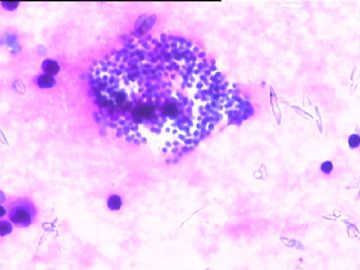

78y,男,胸水。 大家看看那些小于淋巴细胞的东东。

孢子?

图6感觉象是污染的孢子之类的东西。好好回忆一下,制片过程?容器?有没有污染的 可能?

但,最后一图的组织细胞内吞噬现象,怎么解释。

离体的细胞在一定的时间内还是活细胞,所以我推测吞噬细胞可能还是有一定的吞噬功能的。不过,确实也不能就排除了在活体内的微生物感染的可能。结合临床应该能够得到一定程度的澄清。